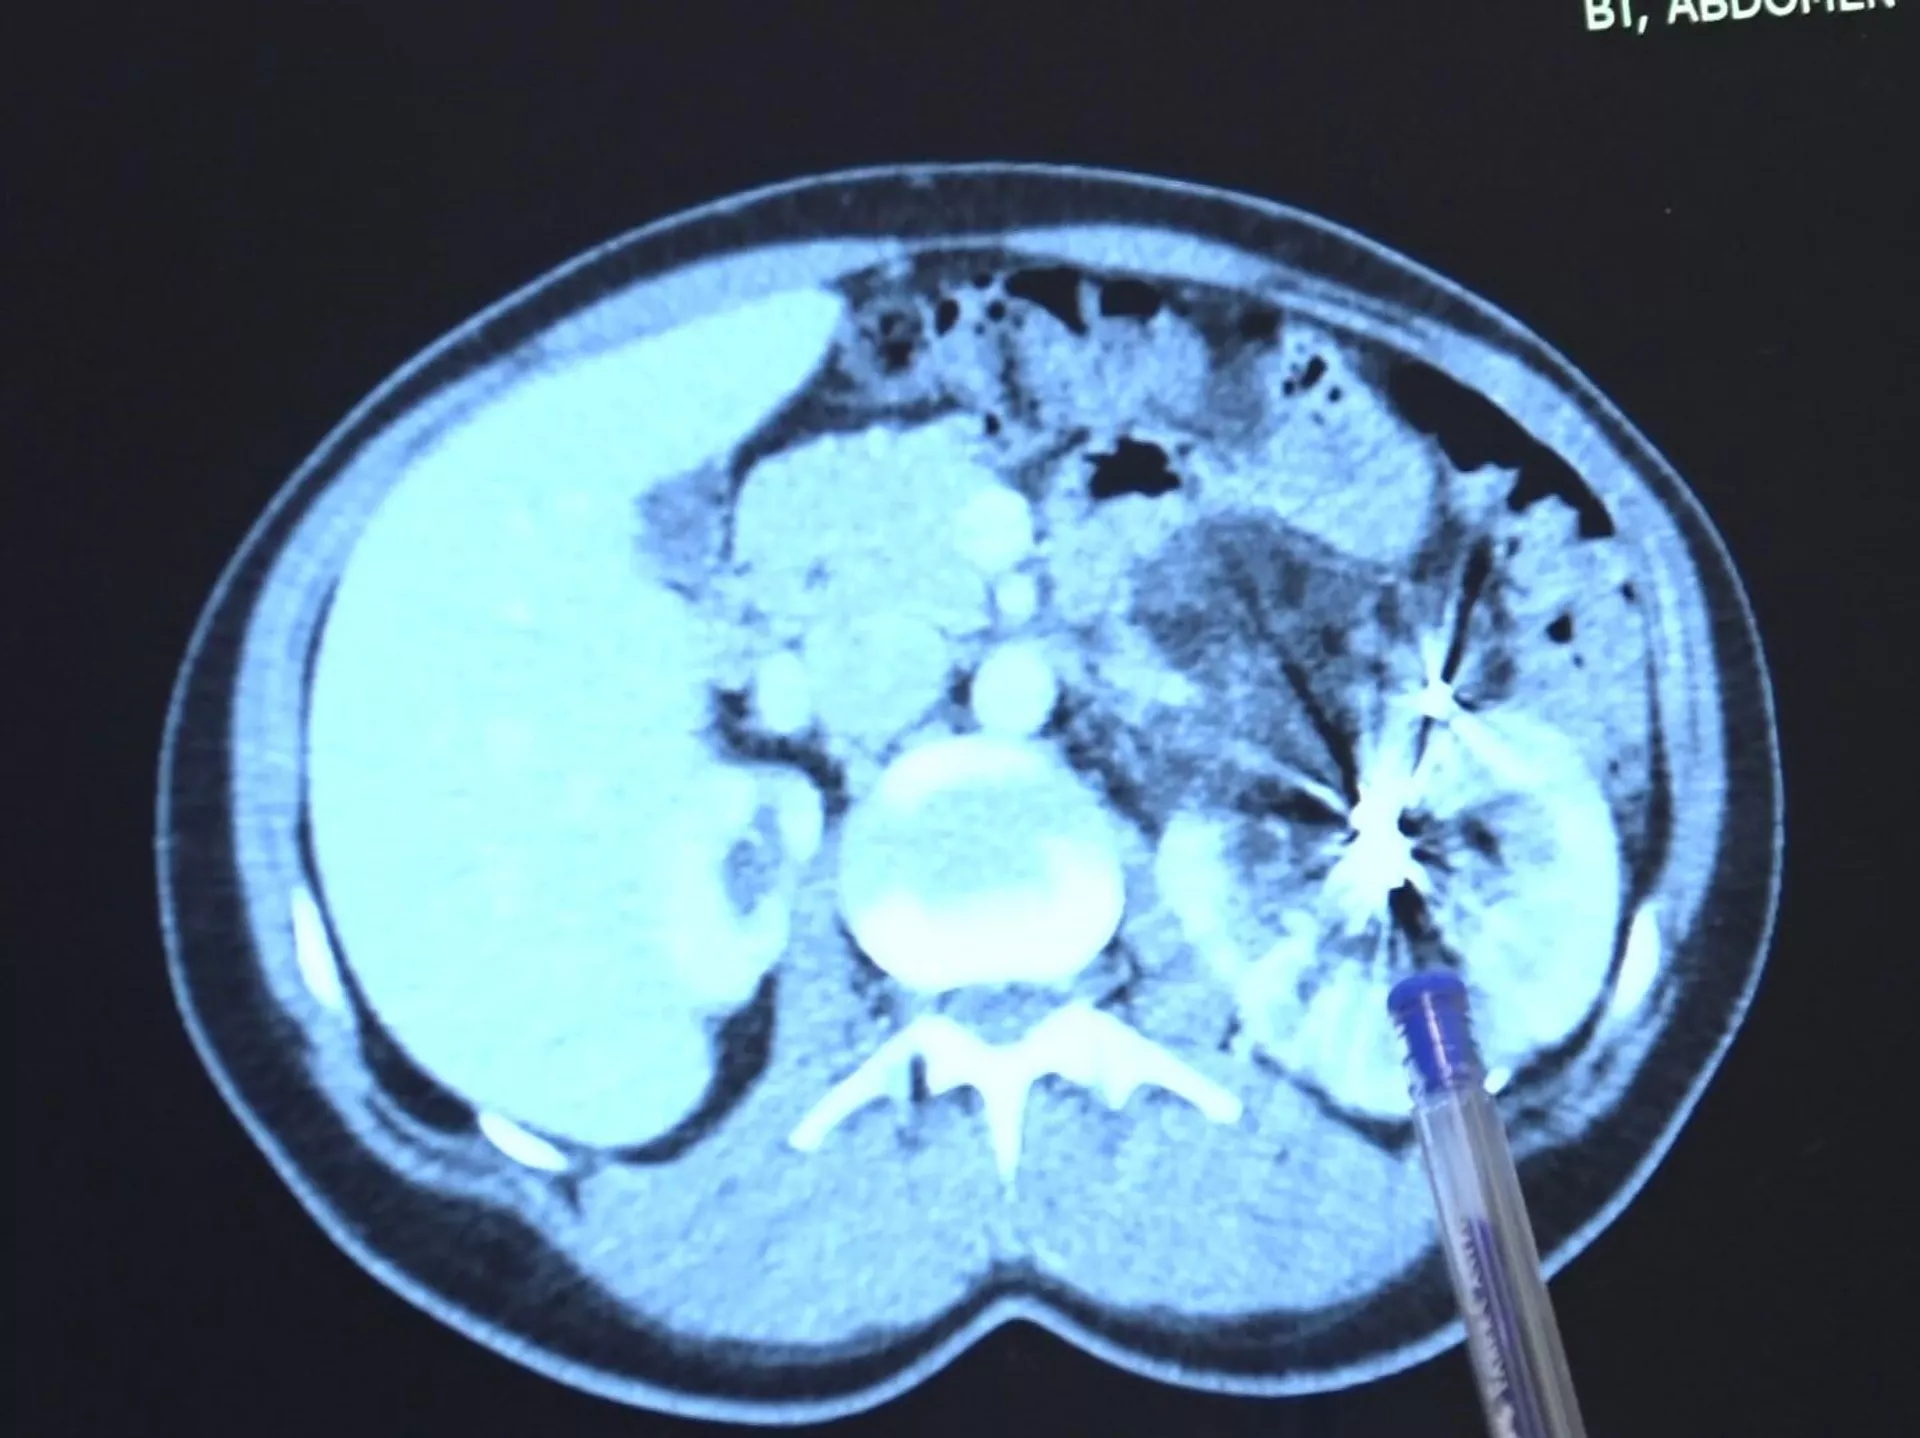

İzmir'de bir kadın bel fıtığı için MR çektirmeye gittiği hastanede tek böbrekli olarak doğduğunu öğrendi. Böbreğinde iyi huylu kitle için yapılan tedavilerin yeterli olmaması üzerine büyüyen kitle 12 santimetreye kadar çıktı. Çözümü Bursa'da bulan kadının, 2 saat süren kapalı ameliyatla sağlığına kavuştuğu bildirildi.

Yıllar sonra çekilen MR da tek böbrekte kitle bulunmuş ve bunun üzerine iyi huylu kitleye iki kere embolizasyon işleminin yapıldığı açıklandı. Kitlenin büyümeye devam etmesiyle gittiği doktorlardan böbreğinin alınması gerektiğini duyan Avcı'nın, Bursa'da 2 saatlik kapalı bir operasyonla sağlığına kavuşturulduğu bildirildi.

Hastanın, sağlam böbreğinde büyüyen iyi huylu 'anjiomyolipomu' adı verilen 12 santimetre boyutunda bir kitlenin tedavisi tamamlandığı bildirildi. Kadınlarda 4 santimetreden büyük anjiomyolipomuların kendiliğinden kanayarak yaşamı tehlikeye atması nedeniyle bu kitlelerin an kısa zamanda alınması büyük önem taşır.